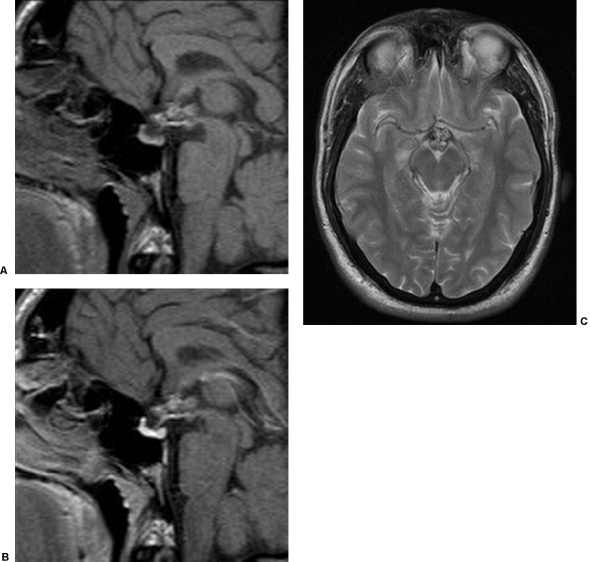

該患者在一家診所接受常規(guī)治療,有1周嚴重視力衰竭和雙顳區(qū)缺損的病史。他被接納,并進行重復核磁共振掃描(圖2).這表明病變的下丘腦/后視交叉部分沒有變化;然而,現(xiàn)在存在相關的信號異常以及前視交叉和后視神經(jīng)的擴張。這些變化與出血性降解產(chǎn)物一致。

圖2:(A)垂體窩的冠狀面t1加權(quán)像和(B)垂體窩的釓后矢狀面t1加權(quán)像和(C)腦軸向t2加權(quán)像(比圖1下1節(jié))。與圖1.1相比,下丘腦病變無變化。更早的出現(xiàn)了信號異常的新領域。這返回t2加權(quán)高強度,同時伴有周圍t2加權(quán)低密度和中央灶狀t1加權(quán)高強度。這擴大了視交叉和視前神經(jīng),而不伴有釓強化。特征與出血性降解產(chǎn)物一致。